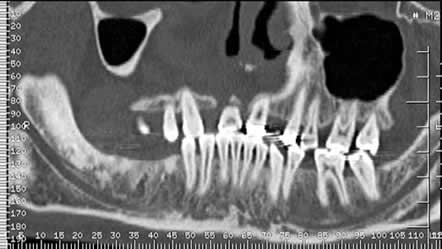

Fig 28. Atrofia ósea.

A: Ortopantografía y B: Panorámica de dentascan. Ausencia de piezas, con atrofia de la cresta alveolar maxilar y mandibular en A y del maxilar en B.